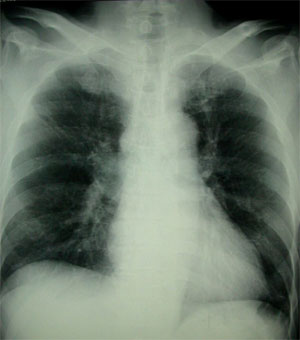

一発診断!一目瞭然!